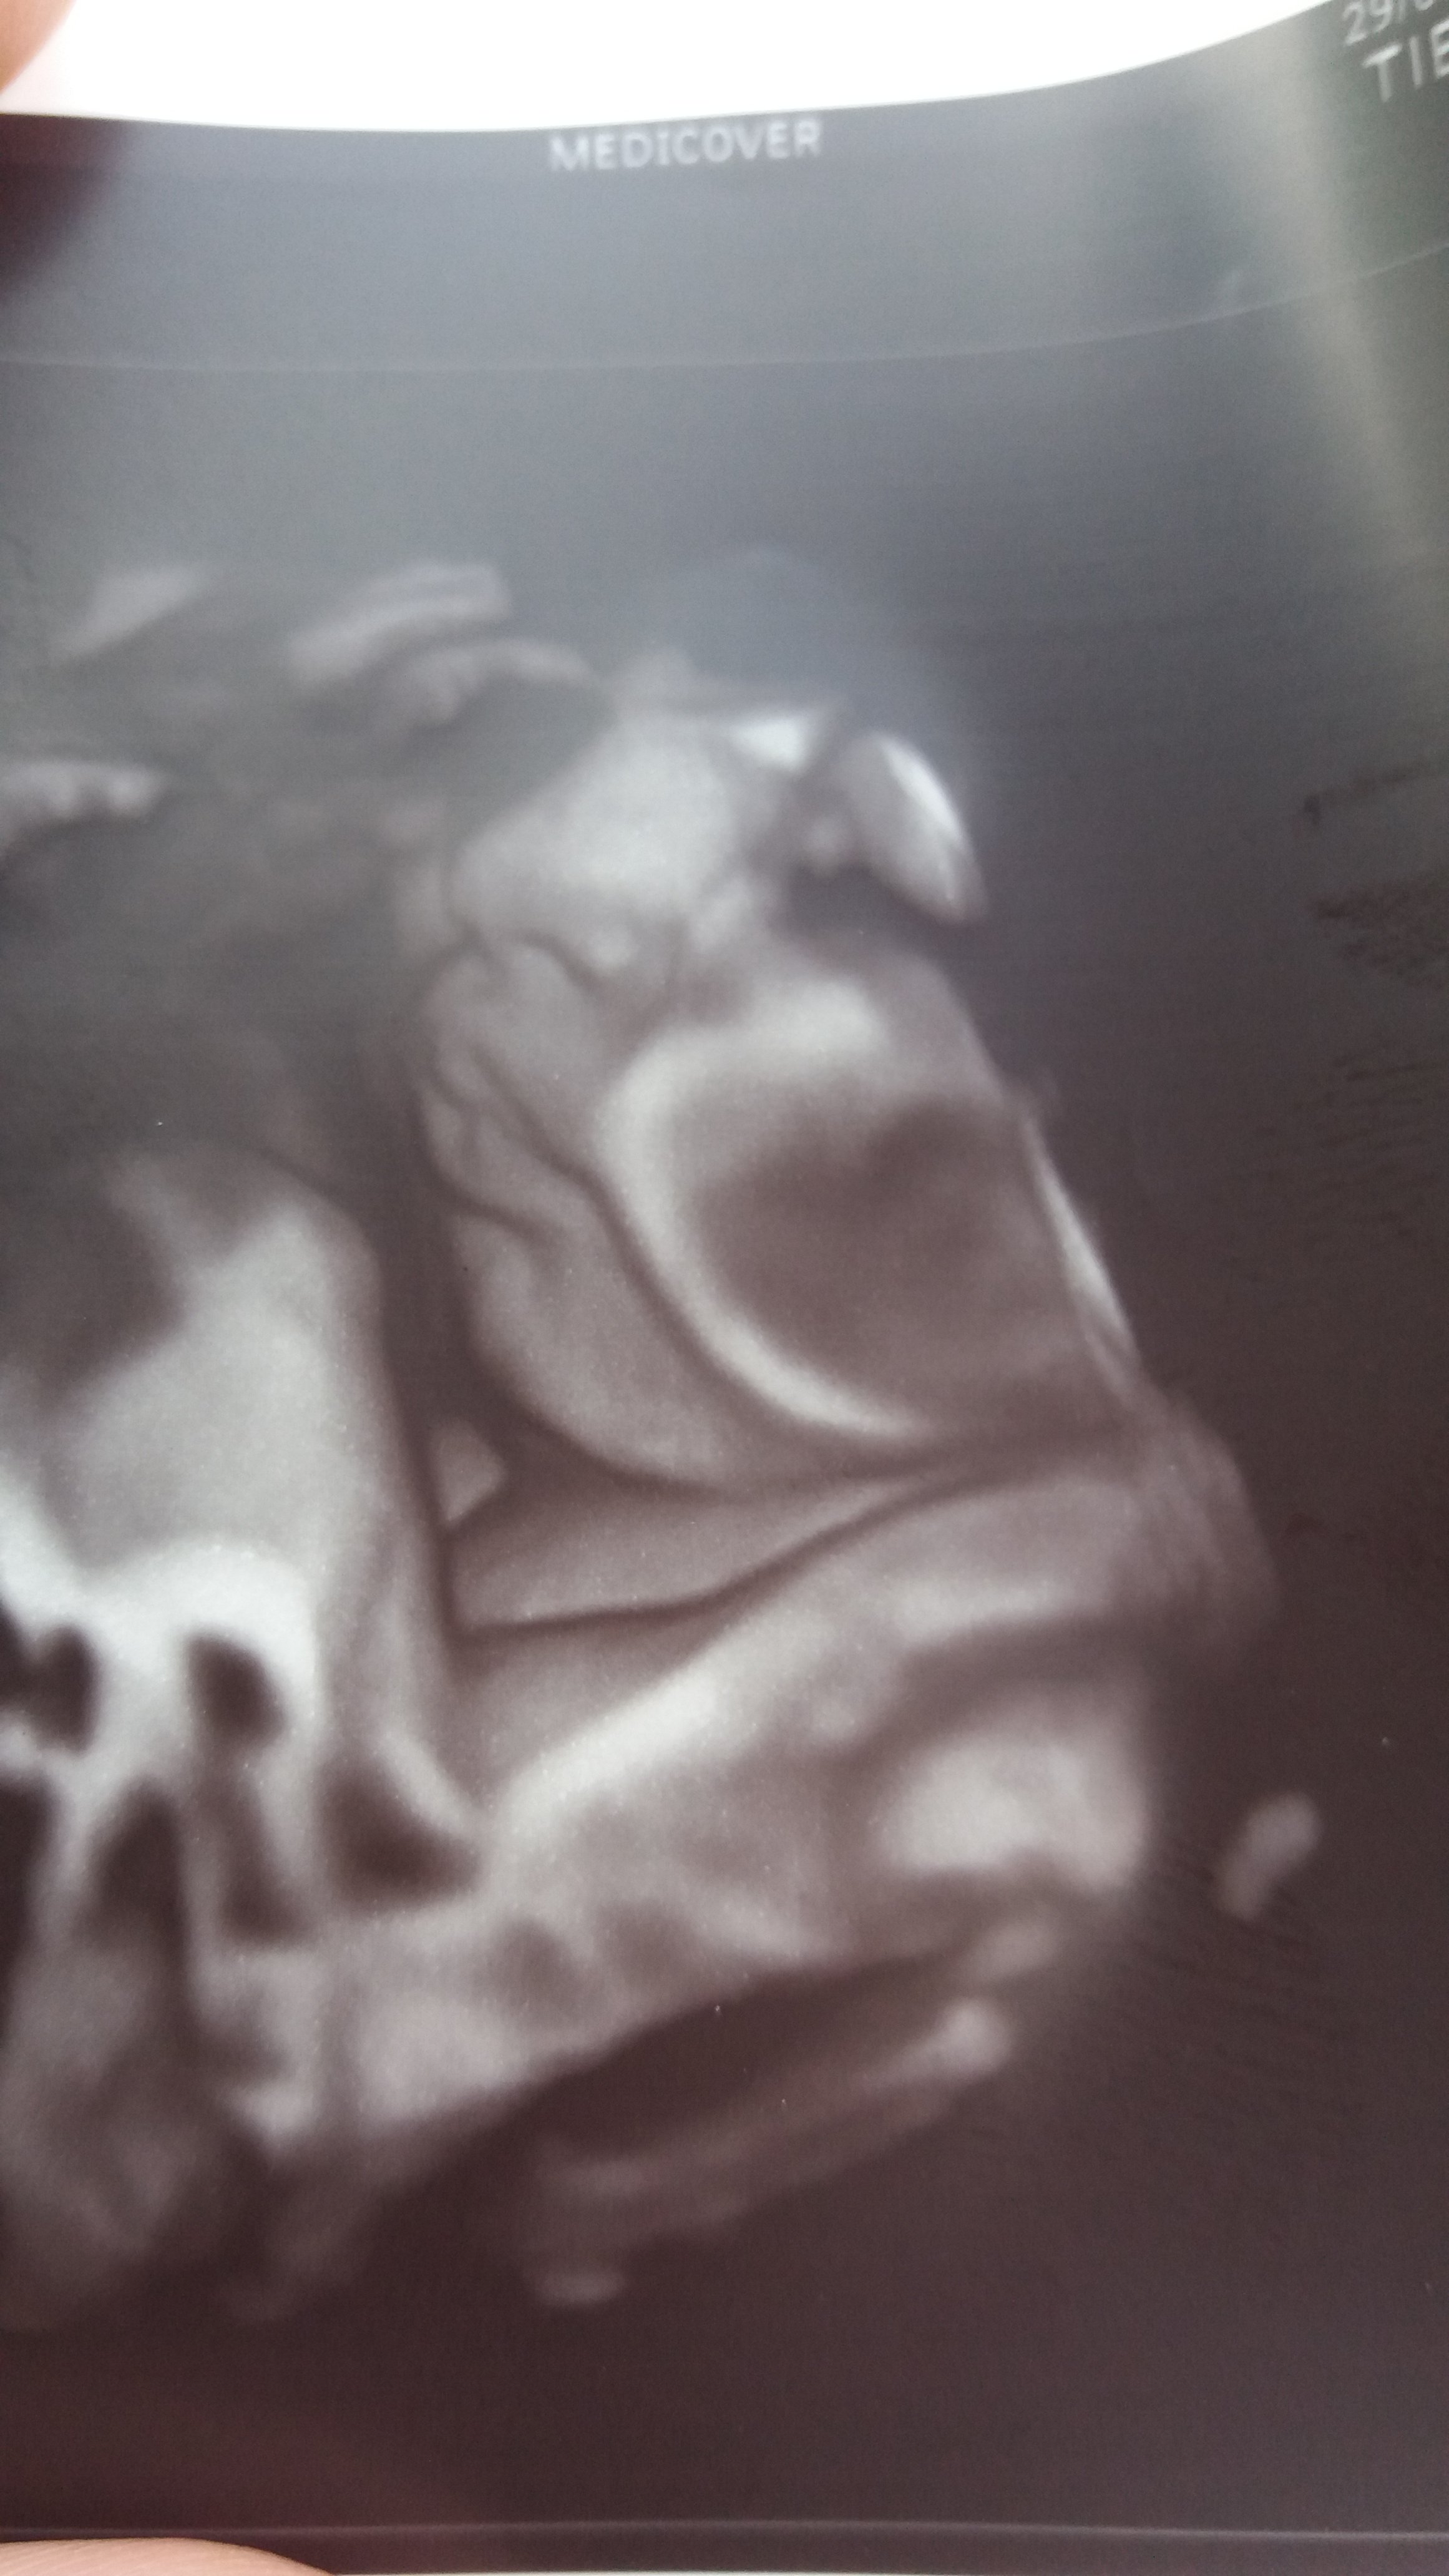

Ja tez chce taka fotke.

Chociaz usteczka zeby bylo widac. Moze akurat jutro bedzie miala kluska dzien dobroci dla matki i nie zasloni sie rekami, pepowina ani sie nie odwroci do kregoslupa.